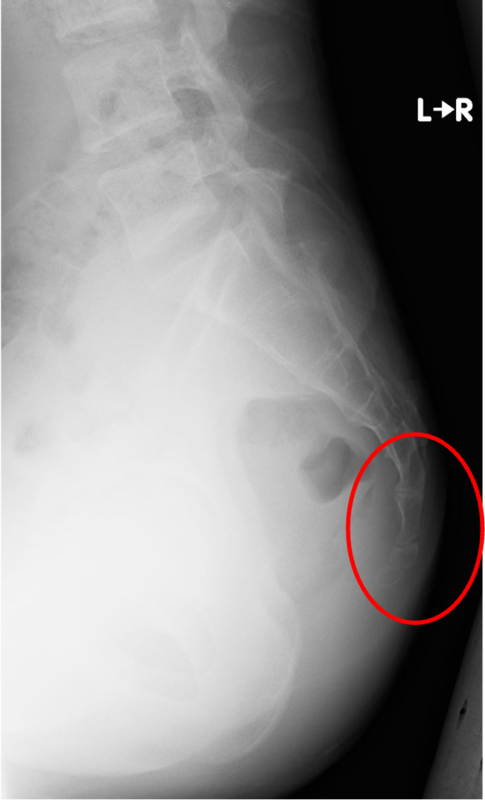

レントゲン画像

赤く囲んだ部分に痛みが出現しています。

特に骨傷などは認めません。